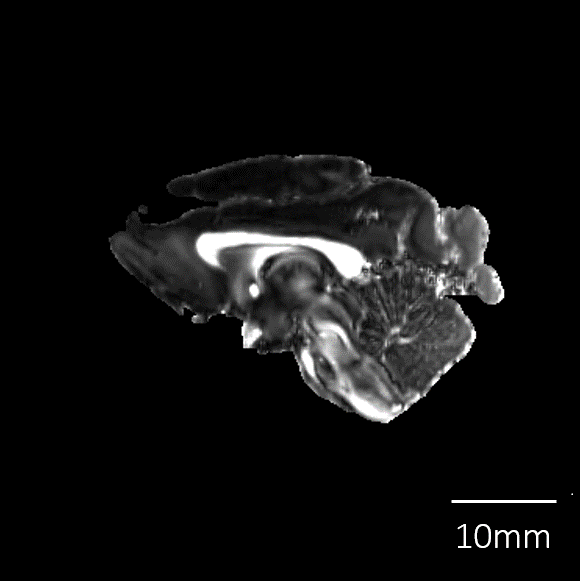

| 剖検番号 | Pr6443 |

![]() |

|

性別 |

メス | |

死亡時年齢 |

20才 | |

| 死亡時体重 | 3,800g | |

| 脳重量 | 71.2g | |

| 脳解剖所見 |

撮像情報 Imaging Condition

| T2強調画像 | 拡散テンソル画像 (DTI) | |

| エコー時間 (TE) (秒) | 7.5 | 20 |

| 繰り返し時間 (RT) (秒) | 700 | 700 |

| 励起回数 (NEX) | 2 | 2 |

| 有効視野 (FOV) (mm) | 80, 64, 48 | 80, 64, 48 |

| マトリクスサイズ | 320, 256, 192 | 160, 128, 96 |

| 空間分解能 (µm) | 0.25, 0.25, 0.25 | 0.5, 0.5, 0.5 |

| b0 | - | 2 |

| 撮像時間 | 5時間 13分 | 57時間 20分 |

脳標本画像

脳表再構成画像 |